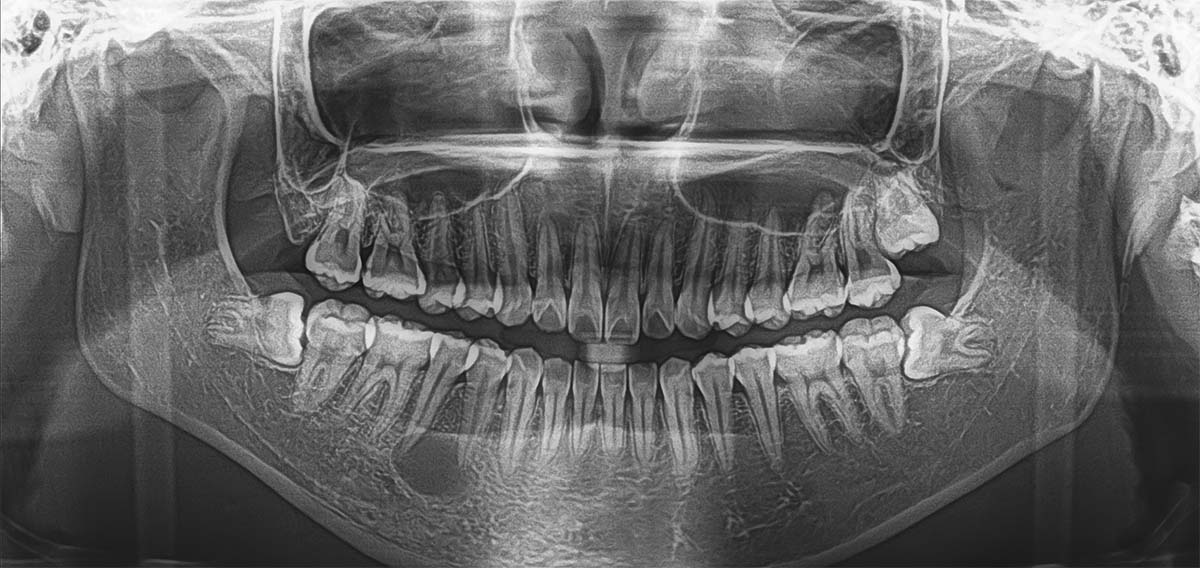

Imágenes panorámicas versátiles

Panoramica de alta definición

La CBCT multifuncional FUXI ofrece a los usuarios una variedad de modos de imágenes panorámicas, incluido el modo estándar, el modo para niños, el modo especial, imagenes de partición, etc., para satisfacer los requisitos de imágenes de diferentes formas de arco mandibular y diferentes ubicaciones clínicas.

Modo infantil

Imágenes panorámicas guidas por IA: el posicionamineto automático del arco dental basado en la tecnología de inteligencia artificial (IA) puede mejorar la precisión del posicionamiento del paciente en las imágenes panorámicas, mejorar la calidad d ela imagen y evitar exámenes repetidos debido a errores de posicionamiento.

Panorama de Partición